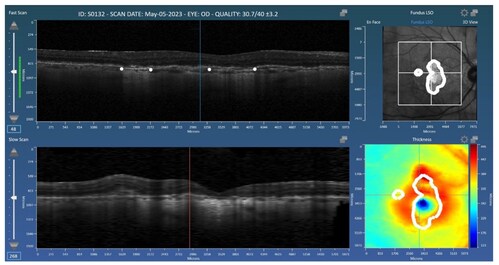

WALTHAM, Mass., Nov. 6, 2025 /PRNewswire-PRWeb/ -- Voiant, a leader in clinical trial imaging solutions, is pleased to announce the publication of a new peer-reviewed study in Diagnostics as part of the Special Issue Updates on the Diagnosis and Management of Retinal Diseases—2nd Edition. The article, titled "Deep Learning-Based Segmentation of Geographic Atrophy: A Multi-Center, Multi-Device Validation in a Real-World Clinical Cohort", presents a deep learning-based method for automated segmentation and quantification of geographic atrophy (GA) in spectral-domain optical coherence tomography (OCT) scans.

The model was trained and validated on real-world clinical data from two major OCT platforms (Spectralis and Cirrus) among patients with and without concurrent neovascular age-related macular degeneration (nAMD). Results from the Spectralis and Cirrus data sets achieved Dice similarity coefficient (DSC) scores of 0.83 and 0.82, respectively, and correlation coefficients (r2) of 0.91 and 0.88, respectively, with manual expert grading. The study concludes that deep learning offers accurate, reproducible GA assessment across diverse imaging conditions and comorbidities. Read the full open-access paper here for more information.

The research leverages Orion, Voiant's cloud-based reading platform developed by Voxeleron, a Voiant Company. Orion supports flexible reading center workflows with advanced editing tools, native file format compatibility, and automated segmentation for retinal layers, GA, and fluid regions. The purpose-built software enables multimodal analysis tools that are validated, reproducible, and tailored to sponsor needs.